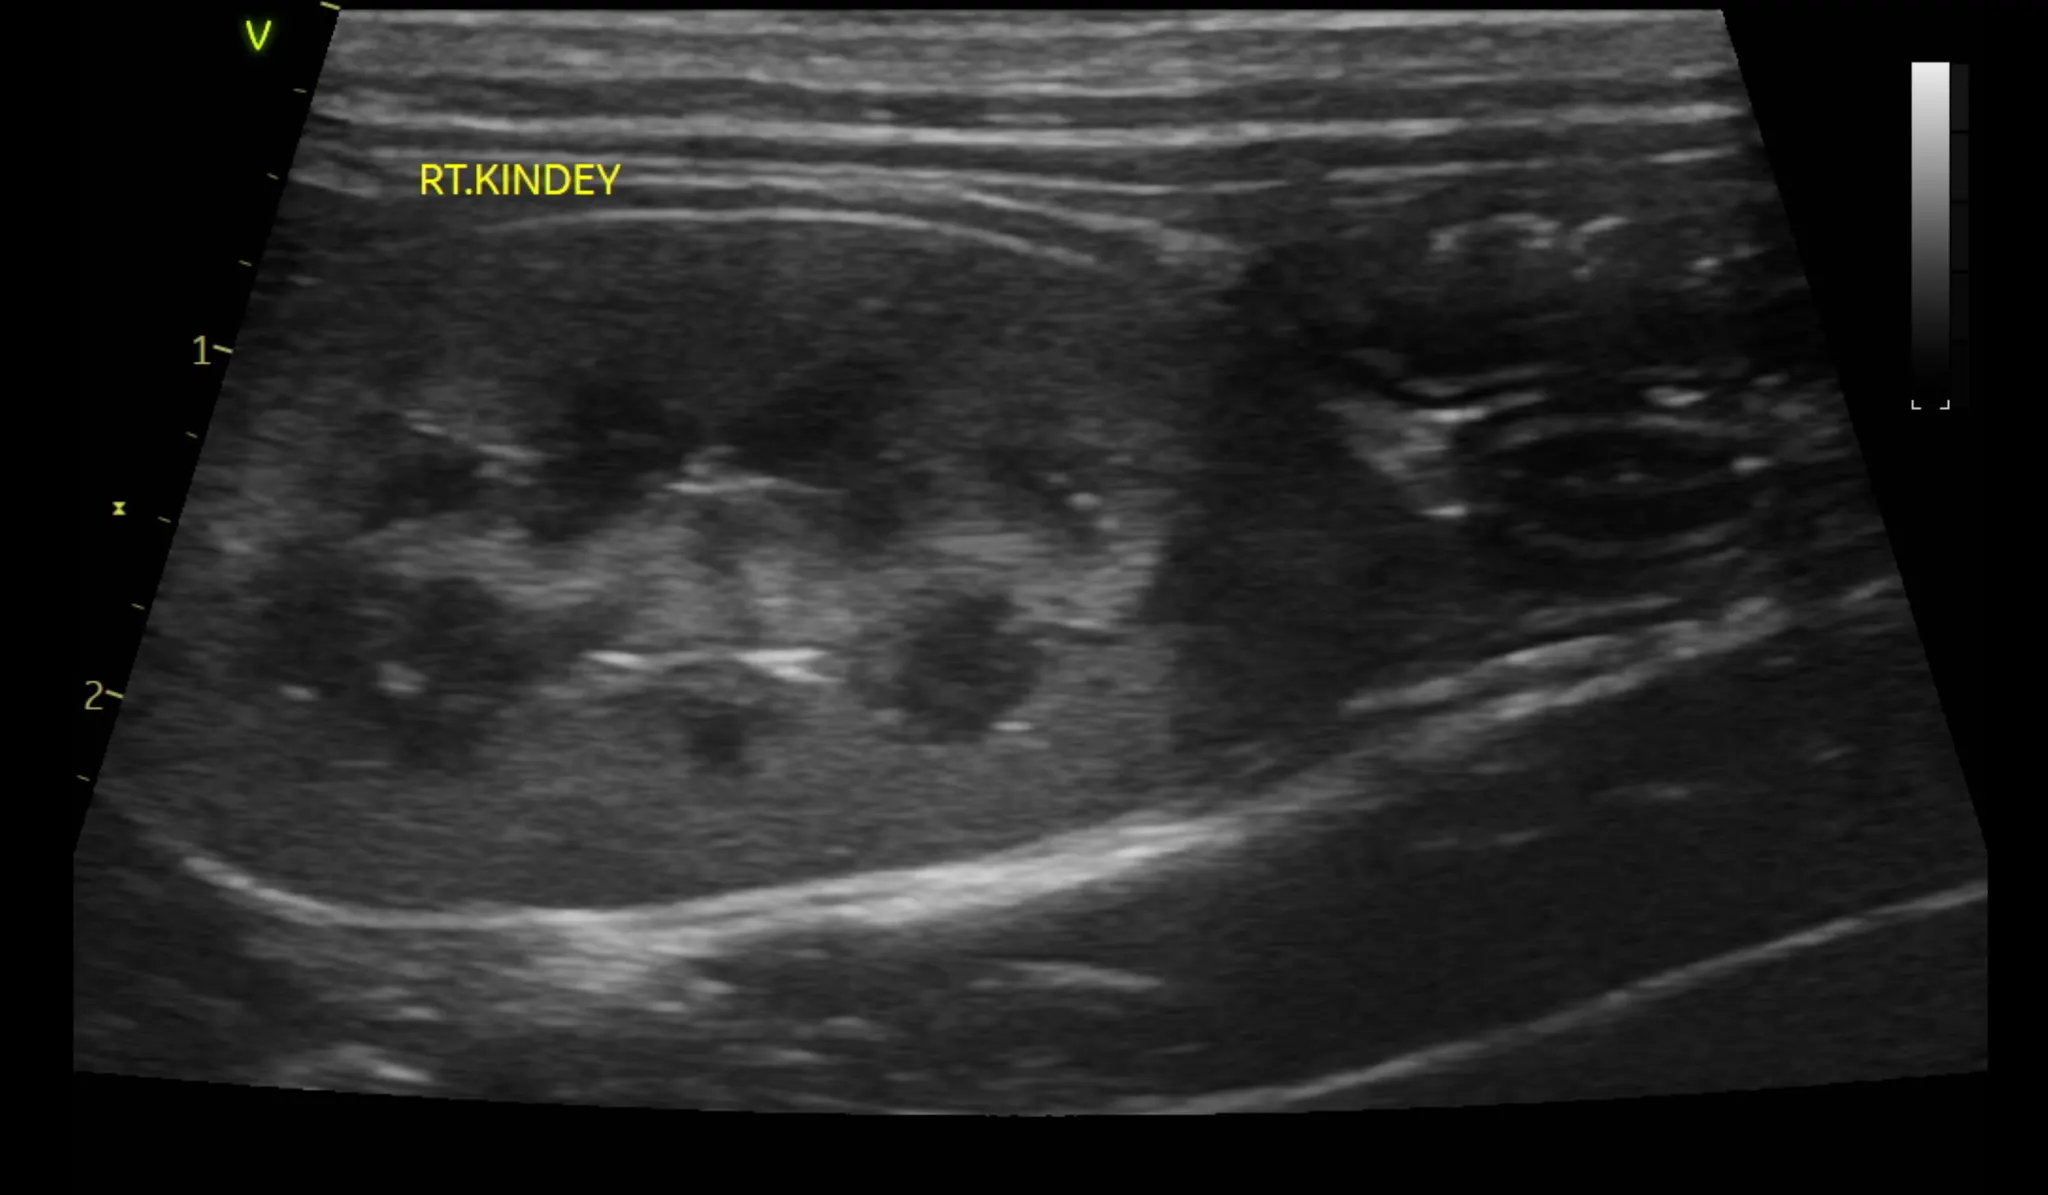

3. 복부 초음파 검사 결과

복부 초음파 검사로는 간, 신장 등 복부 장기의 모양과 결석, 종양등의 이상여부를 알 수 있습니다.

또한 방광 결석, 다낭포성 신장질환 같은 고양이에서 잘 생기는 질환의 경우 초음파 검사로만 알 수 있으므로 매우 중요한 검사 중 하나입니다.

복부 초음파 검사 상 특이사항은 발견되지 않았습니다.

1년 주기로 검사를 추천드립니다.